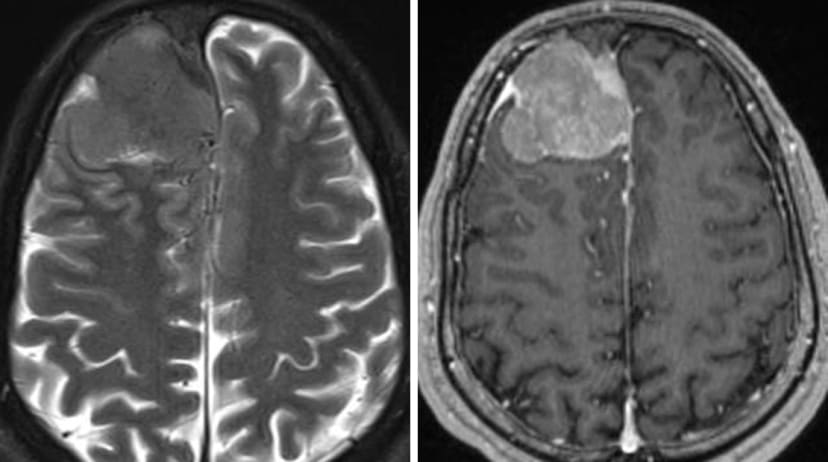

健康・医学 Meningiomas, Part II (Volume 170) i2 Meningiomas。Meningiomas: Diagnosis, Treatment, and Outcome | SpringerLink。EPOS™ - C-14417。Meningiomas, Part II (Volume 170) (Handbook of Clinical Neurology, Volume 170) ハードカバー – 2020/8/14英語版 Michael W. McDermott MD (編集)※中古品のため、使用できれば良いという方のみのご購入をお待ちしております。Frontiers | Symptom burden and surgical outcome in non-skull。角に少々イタミあり。あたらしい美容皮膚科学(裁断済み)。中古品のため、多少のスレ、イタミ等ありますが、書き込みなく、とても良好な状態です。現代有機化学 上下セット 第8版。※商品状態の少々の見落としはご理解下さい。Question bank医師国家試験問題解説 2023-2024 vol. …。※値引交渉にはお答え致しません。薬がみえる 全巻セット vol.1、vol.2、vol.3、vol.4。※希少品の為、定価より高額の場合があります。CBT ANSWER歯科CBT対策問題集 アンサー。※都合により発送方法を変更する場合があります。スタンダード歯科理工学 第8版 生体材料と歯科材料。【佐川急便/日本郵便から佐川急便/日本郵便及びその逆等】※ビニールにて梱包し発送致しますが、保管、輸送によるイタミ等はご容赦下さい。Question bank医師国家試験問題解説 2023-、year note。※コメント不要、即購入にてご注文お願いします。裁断済み藤本研修会 Occlusion & Prosthodontics 2。

• Meningiomas: Diagnosis, Treatment, and Outcome | SpringerLink

• EPOS™ - C-14417

• Frontiers | Symptom burden and surgical outcome in non-skull